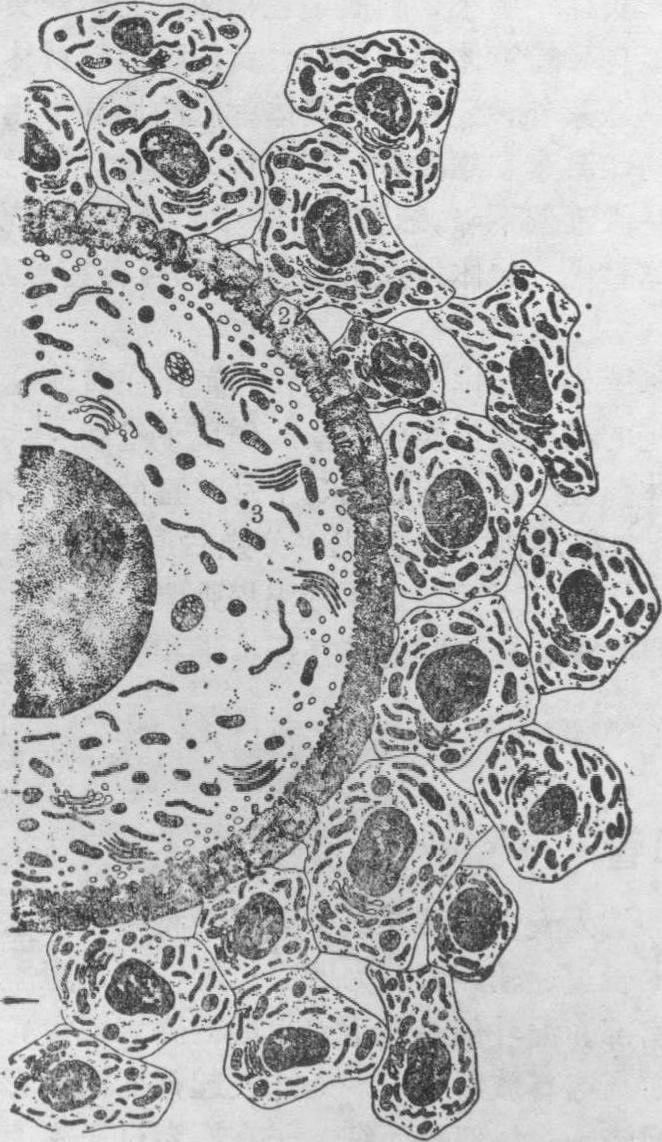

初级卵泡 体积较原始卵泡大,由初级卵母细胞及其周围的单层立方或多层卵泡细胞构成。卵母细胞长大。胞质中线粒体增多;高尔基复合体由一个增加为多个,并由核旁分散到初级卵母细胞的外围;粗面内质网发达,游离核糖体增加;出现少数脂滴。当初级卵母细胞直径达50~80μm时,在卵母细胞与卵泡细胞之间出现一层含糖蛋白的嗜酸性胶质膜称透明带,由卵母细胞和卵泡细胞共同分泌形成。电镜下可见卵母细胞表面伸出的微绒毛和卵泡细胞的突起伸入透明带内。微绒毛和突起紧密接触,有利于卵泡细胞将营养物质输送给卵母细胞(图1)。卵泡细胞一般为多角形或立方形,排列成上皮样。当卵泡生长时,卵泡细胞内游离核糖体和粗面内质网增多,高尔基复合体更显著,这些结构与蛋白质合成有关,适应于卵泡生长时卵泡细胞增殖。卵泡细胞的细胞质外围含有微丝束。这些微丝束并伸入细胞突起,与排卵时卵泡细胞突起缩回有关。卵泡细胞间有多种细胞连接,缝隙连接在卵泡生长时协调各细胞间的功能。卵泡继续长大时,围绕卵泡的卵巢基质形成卵泡膜。不久卵泡膜又分化为内外两层。内层含有较多的多边形或梭形的分泌细胞,电镜下细胞具有分泌类固醇细胞的结构特点,此层血管较丰富。外层主要是结缔组织,含纤维多,血管较少。卵泡膜与卵泡细胞间为基膜。

图1 卵母细胞、透明带和卵泡细胞的超微结构

1.卵泡细胞 2.透明带 3.卵母细胞